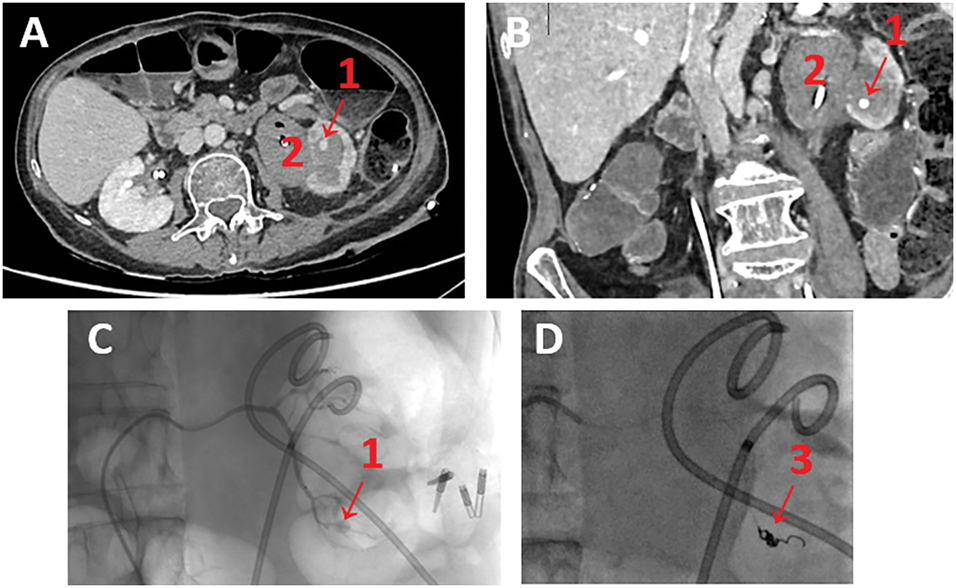

On day 1 of insertion of the new left nephrostomy tube, the patient developed visible haematuria. The patient was haemodynamically stable, and no blood loss was found. An arterial phase contrast-enhanced abdominopelvic CT-scan revealed a left inferior polar false aneurysm associated with extensive clotting of the cavities, likely related to the first renal puncture-dilatation (please see Figure 3A,B).

FIGURE 3. Visualisation of pseudoaneurysm. (A) Injected abdominopelvic CT-scan showing left inferior polar arterial pseudoaneurysm—axial view; (B) Injected abdominopelvic CT-scan showing left inferior polar arterial pseudoaneurysm—coronal view; (C,D) Intraoperative arteriography of left renal false aneurysm embolization. Note: (1) arterial pseudoaneurysm, (2) extensive clotting of the cavities, (3) Coil.

Super-elective radioembolization was performed by the interventional radiologists on the same day without any immediate complications (please see Figure 3C and D).